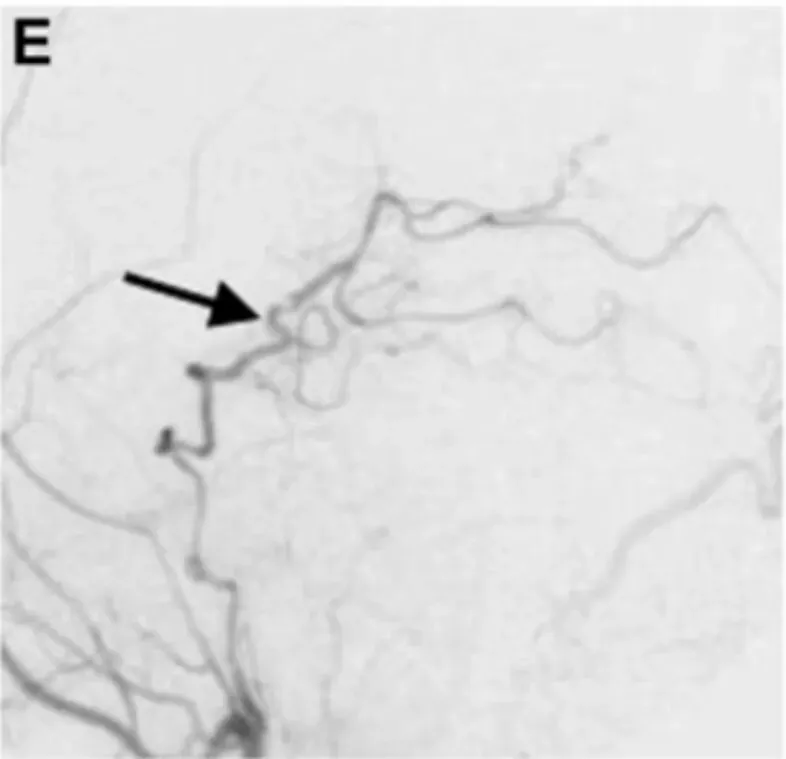

18天后,真相终于浮出水面。延迟血管造影显示,在患者左侧P1-P2段,一个夹层动脉瘤正在悄然生长,并呈现出狭窄特征。此时,医生们才真正“抓到了”威胁他生命的元凶。

在确诊后的第20天,川岛教授团队决定为患者实施手术。此时,动脉瘤已经延伸到P2段后部,情况更加复杂。

术后一周的血管造影结果显示:通过旁路到达左侧PCA区域的血流良好,动脉瘤完全被排除。